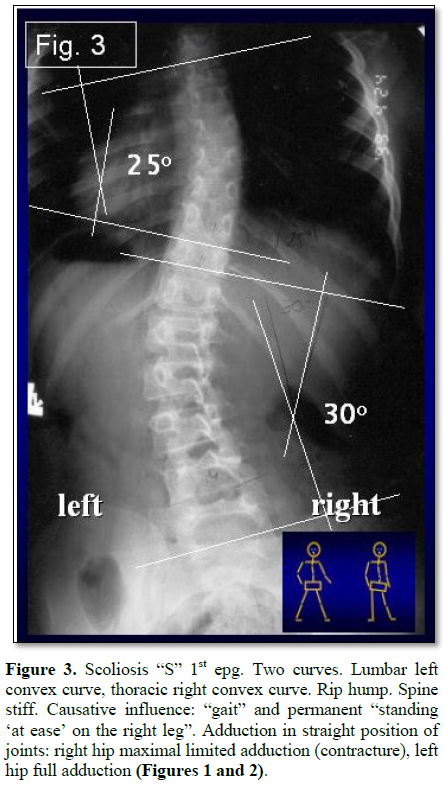

1. Scoliosis “S” 1st etiopathological group (epg) (Figure 3) - double curve. Right hip adduction is 0 or (-) 5 (-) 10 degrees. Left hip adduction is 30 to 50 degrees. Stiff spine (3D). Rip hump on the right side of thorax. Connection with gait and standing.

2. “At ease” on the right leg. There is a large asymmetry of movements of hips. The absent/very limited movement of the right hip is transmitted to the pelvis and the spine. Next, a permanent rotation movement in infer-vertebral joints in a form of distortion appears, in every step – the result is stiffness of the spine. Because of the asymmetrical standing, longer on the right leg – the loading on the right leg lead to the development of curves.

Scoliosis “S” in 1st type (Figure 3). In X-ray examination of young people, the rotation deformity of the spine comes first. The processi spinosi are twisted to the side – in lumbar spine to the right side, in thoracic part – to the left side, and this occurs deep under the skin. Clinically the spine is stiff.